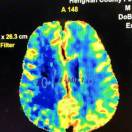

王毅翔 香港中文大学医学院 Diffusion weighted imaging and apparent diffusion coefficient (ADC): what they really tell us 影像及介入放射学系